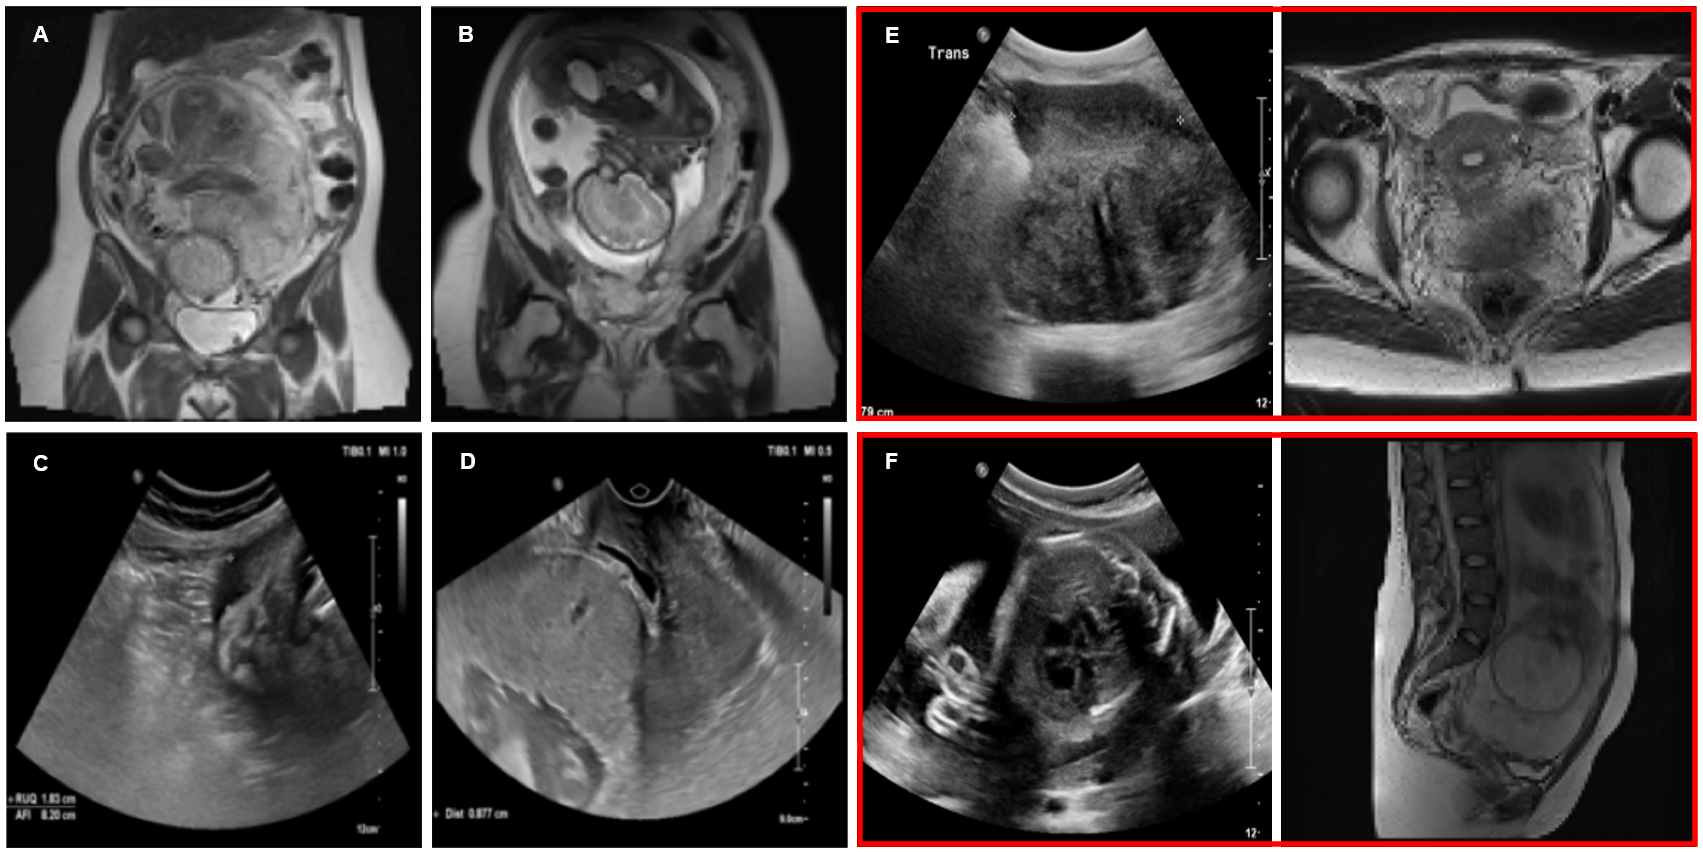

A retrospective cohort of patients’ data, collected in collaboration with the Department of Fetal Medicine at King Abdulaziz University Hospital, was used in this study. All patients’ data were collected and used in accordance with institutional guidelines and ethical standards. Ethical approval was secured prior to the start of the study, and strict measures were taken to ensure patient confidentiality and compliance with data privacy regulations. A preliminary review of the health records in the hospital revealed a high proportion of patients who had been assessed with suspected PAS disorders. After applying rigorous inclusion criteria to select cases with confirmed diagnostic outcomes and sufficient image quality for computational analysis, the initial data comprised 1,293 T2WI MRI scans and 1,143 US images. Figure 1 presents a few examples of the MRI and US collections, with the MRI displaying a single slice of the 3D scan. On MRI, PAS is commonly identified by intraplacental dark bands, interruption of the myometrial border and abnormal vascularity (Figure 1B), where as non-PAS cases show smooth uninterrupted utero-placental surface (Figure 1A). On US, PAS cases (Figure 1D) often present prominent irregular spaces of various sizes in placenta known as placental lacunae, thinning of myometrial thickness and loss of retroplacental clear space, while non-PAS image retains a uniform placental appearance and intact retroplacental zone (Figure 1C). The multimodal image pairs (Figure 1E-F) further highlight the complementary diagnostic information provided by MRI and US for distinguishing PAS-positive and non-PAS cases [Romeo_2021, Ali_2025]. The data collection was intended to represent a wide range of patients, both confirmed PAS and Normal (non-PAS), to develop robust and generalizable deep learning models that can perform accurate diagnosis in a clinical environment.

Figure 1: Example of non-PAS MRI (A), PAS-positive MRI (B), non-PAS US (C), PAS-positive US (D), non-PAS multimodal pair (E), and PAS-positive multimodal pair (F).